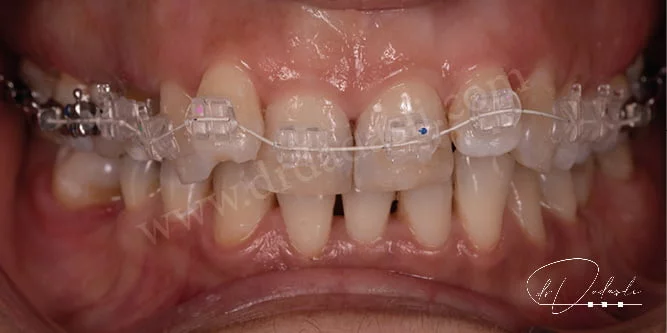

Sabit ortodontik apareyler – ortodontik tedavi amacıyla en yaygın olarak kullanılan apareylerdir. Dişlerin üzerine yapıştırılan braketler (Şekil 11) bu apareylere en iyi örnektir. Bazen arka dişlere band dediğimiz, dişi çepeçevre saran ve braketle aynı işlevi gören küçük apareyler yapıştırabilmektedir. Ark telleri dediğimiz diş telleri ise braketlerin/bandların içinden geçen ve dişleri hareket ettirmemize yardımcı olan bileşenlerdir. Doktor ark telini aktive ederek (sıkarak) dişe uygulanan kuvveti artırmaktadır. Bu aktivasyonlar genellikle 4-6 hafta arası yapılmaktadır. Modern braketler daha küçük, daha hafif ve eski braketlere göre daha az gözükmektedir.

Braketlerin üzerine takılan elastikler (bu elastiklere ligatür denmektedir) farklı renklerde olabilmektedir (Şekil 12), istenirse metal renginde gri elastikler (Şekil 10) de takılabilir. Metal braketler dışında porselen/safir braketler de bulunmaktadır (Şekil 13 ve Şekil 14).